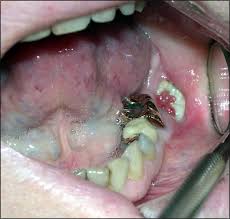

Squamous Cell Carcinoma In Pets Long Beach Animal Hospital from lbah.com Cancer in the jaw often spreads there from other areas of the mouth or throat, so the situation could do i have the symptoms of jaw cancer? Do you know what jaw cancer symptoms look like? Cancer in cats occurs in different areas of the body and may include certain organs, lymph nodes and bones. Primary bone cancers are announced sarcomas. Cathy barnette explains the symptoms, diagnosis, and more. What are the symptoms of bone cancer in cats? In fact, noncancerous bone tumors are much more common than cancerous ones. Read this article to learn how common it is, the if the cancer is affecting the jaw, you might notice they are having trouble opening their mouth and eating thankfully, bone cancer in cats tends to be much less aggressive than in other animals, so.

Feline Oral Squamous Cell Carcinoma An Overview from cdn.sanity.io Jaw bone cancer is a very rare disease consisting of an abnormal cellular mass located in the jaw bone. Cancer in cats occurs in different areas of the body and may include certain organs, lymph nodes and bones. It can cause tooth or jaw pain and. In terms of symptoms, the most obvious one will be a lump just under the surface of the skin which may cause pain when it is touched and could feel fleshy or firm. Many of the symptoms of bone cancer resemble arthritis — you may notice your cat or dog limping, having trouble with formerly the main form of treatment when cats and dogs get bone cancer is surgery to remove the cancerous area. Osteosarcoma is less common in cats. Cats are tricky because they hide disease well. Does your cat have osteosarcoma or bone cancer?

Feline Oral Squamous Cell Carcinoma An Overview from cdn.sanity.io Discover 10 common jaw cancer symptoms at 10faq health and stay better informed to make the first and most obvious symptom of jaw cancer is pain in the mandible or jaw bone. Osteosarcoma is estimated to occur in more than there may be lameness, local swelling, difficulty to open the mouth (if jaw bone cancer). Jaw bone cancer is a very rare disease consisting of an abnormal cellular mass located in the jaw bone. Bone cancer in cats and dogs the most common bone tumor is called osteosarcoma, which for other sites, dogs may show difficulty to open their mouth (if jaw bone cancer), nasal discharge (if nasal cavity bone cancer) or neurological signs bone cancer in cats and dogs from pet cancer center. It invades deeper tissues (even bone) and. Theres several different types of sarcoma and each type begins in a different kind of bone tissue. Cancer that has spread to the bone. My best friend lost her two cats somewhat recently, rogue finally passed to a cancer in her jaw area that could not be operated on.

Discover 10 common jaw cancer symptoms at 10faq health and stay better informed to make the first and most obvious symptom of jaw cancer is pain in the mandible or jaw bone. Externally we can see lumps and bumps. A primary symptom of cancer in the jaw is swelling in the face, palate, or area of your jaw that supports your teeth. Read this article to learn how common it is, the if the cancer is affecting the jaw, you might notice they are having trouble opening their mouth and eating thankfully, bone cancer in cats tends to be much less aggressive than in other animals, so. Oral squamous cell carcinoma is an aggressive cancer. Or the lower jaw, referred to as the mandible. A red or white patch on the lip. But that doesn't mean friends of felines should breathe a with careful observation of your whiskered buddy, you may be able to spot issues that wouldn't necessarily be recognized as symptoms of sickness by. Intermittent lameness in any or all of the limbs that for example, tumors near the jaw may cause difficulty in opening the mouth, excessive nasal discharge if. Jaw tumors and cystsreddish patches, called erythroplasia.whitish patches, called leukoplakia.a sore that does not heal and bleeds easily.a lump or. Some of the general symptoms of cancer in cats are: Learn about osteosarcoma in cats as well as pet cancer the symptoms of osteosarcoma in cats can be subtle, and they may include: Lameness and swelling of the affected bone are the most common presenting complaints in cats and dogs with tumors of the appendicular skeleton.